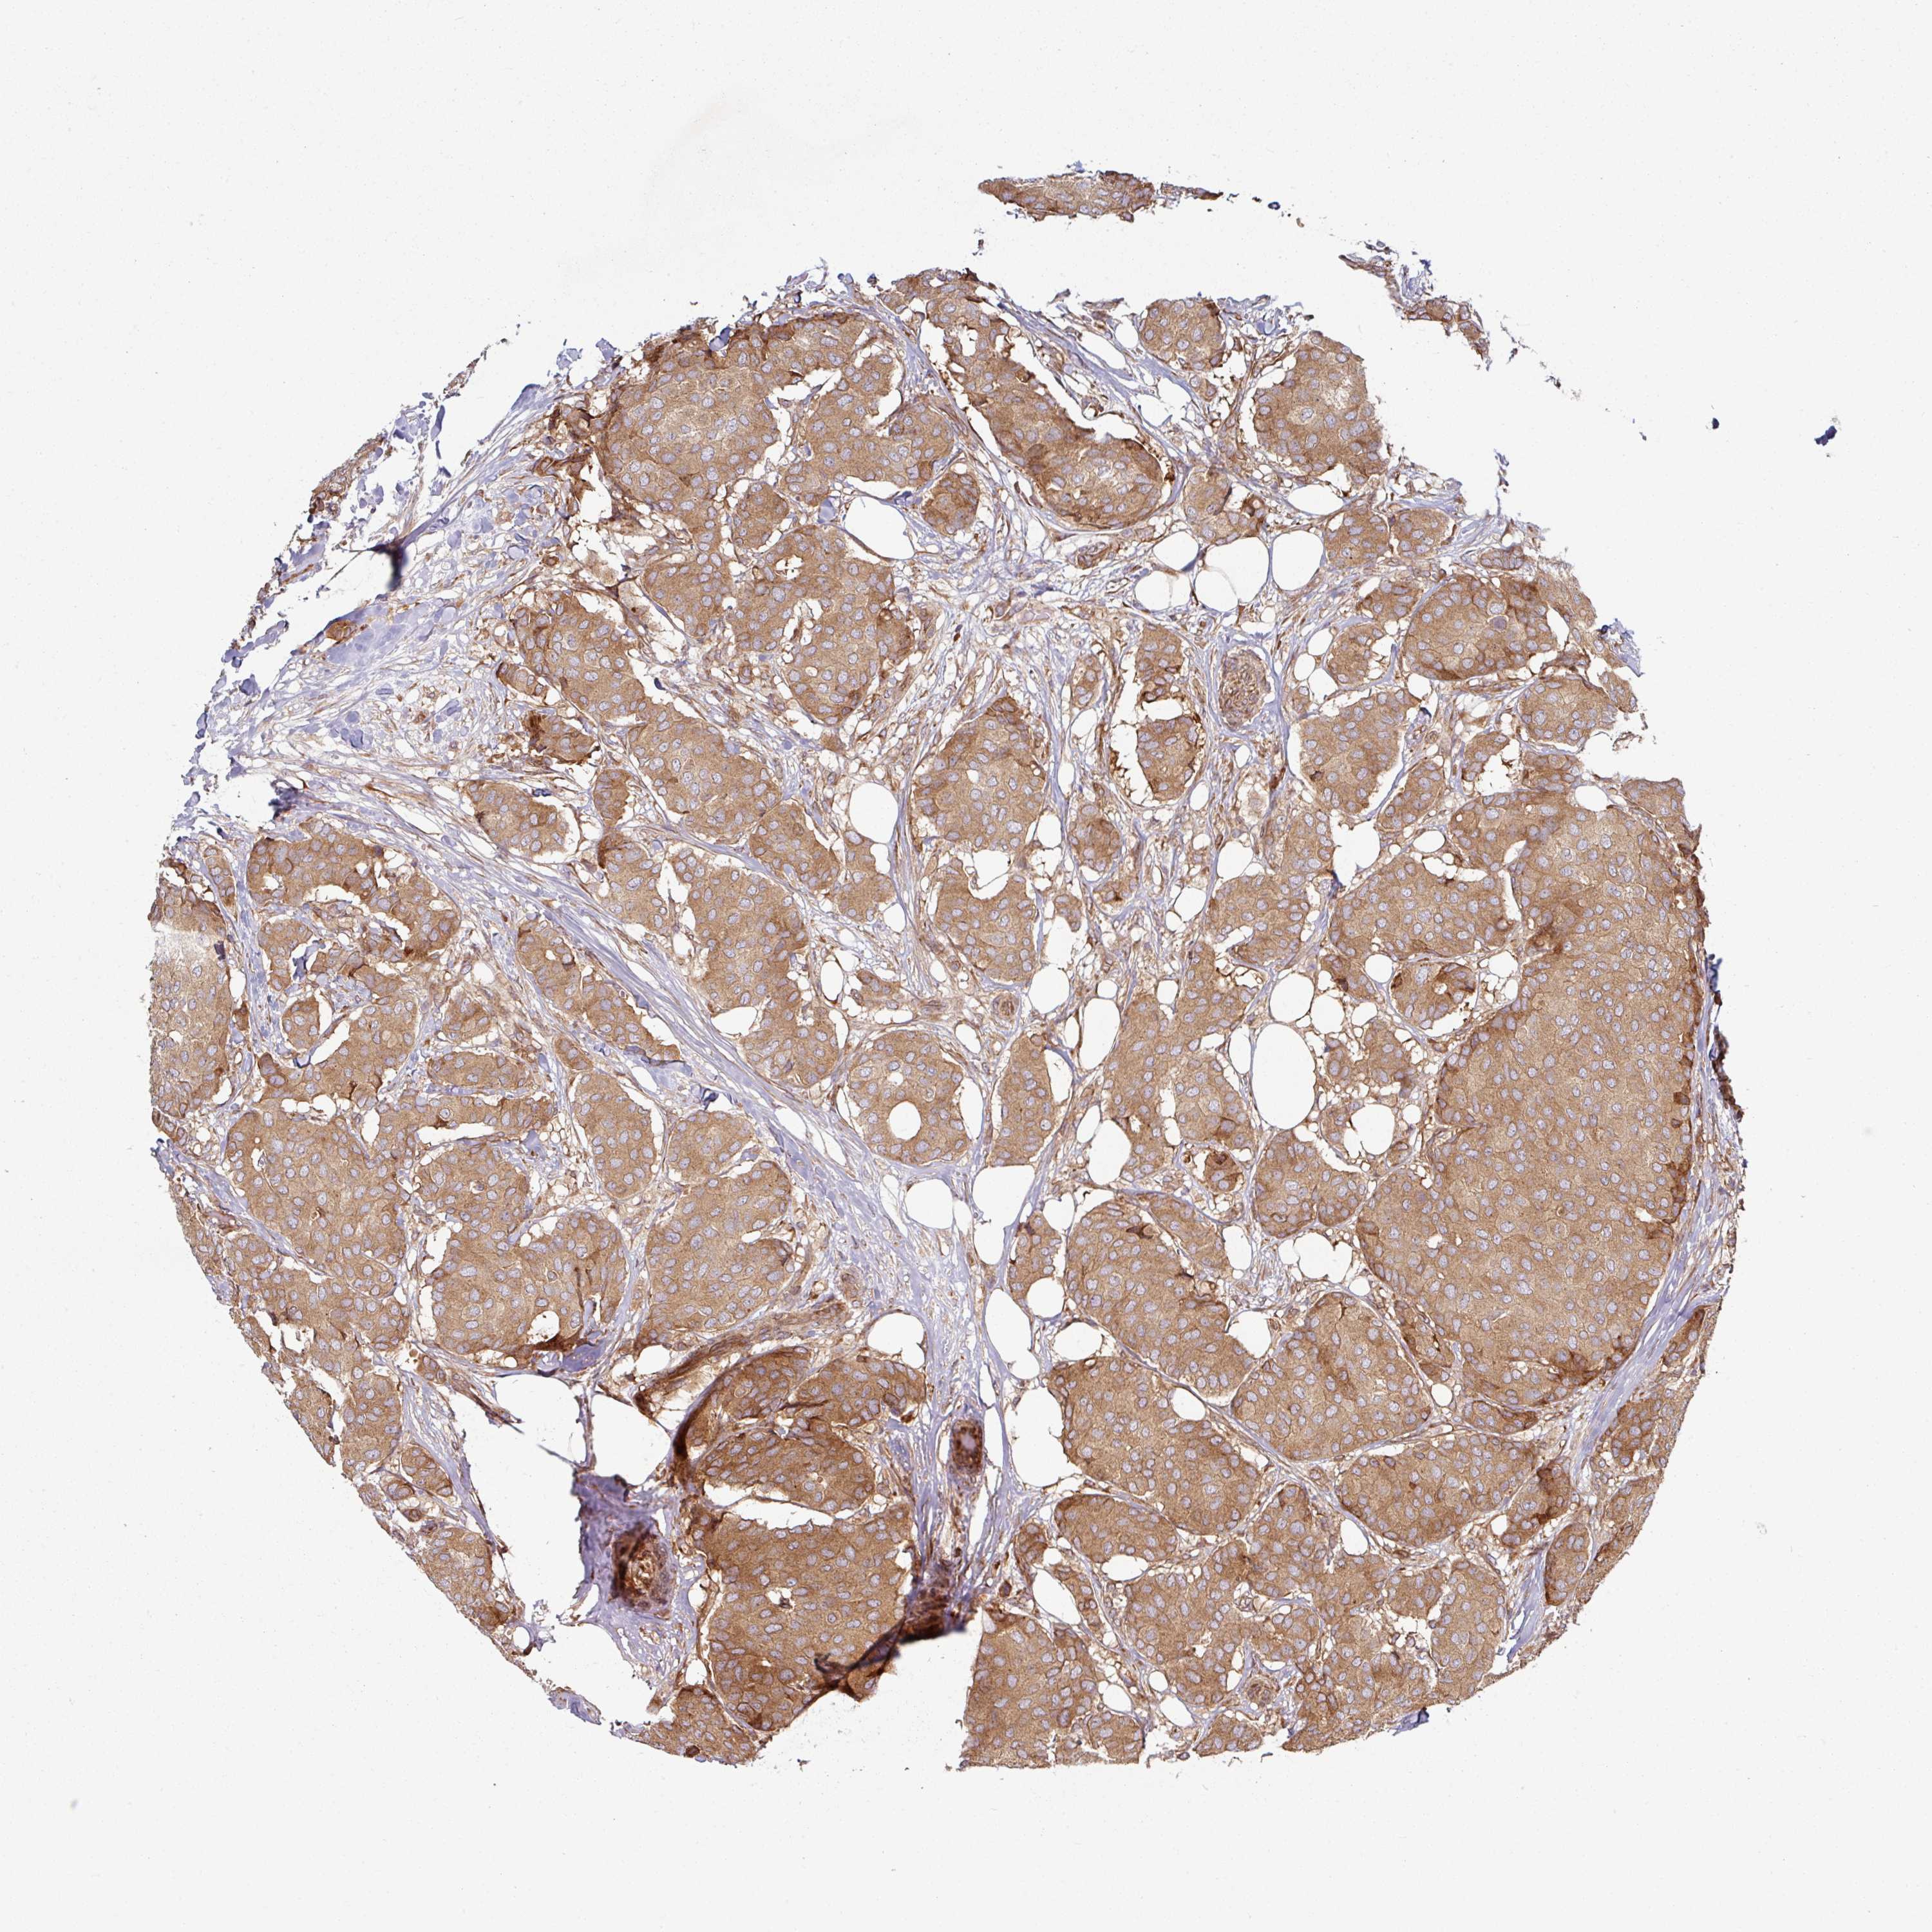

CANCER BREAST CANCER Show tissue menu

BRCA TCGA BRCA VALIDATION PROTEIN EXPRESSION